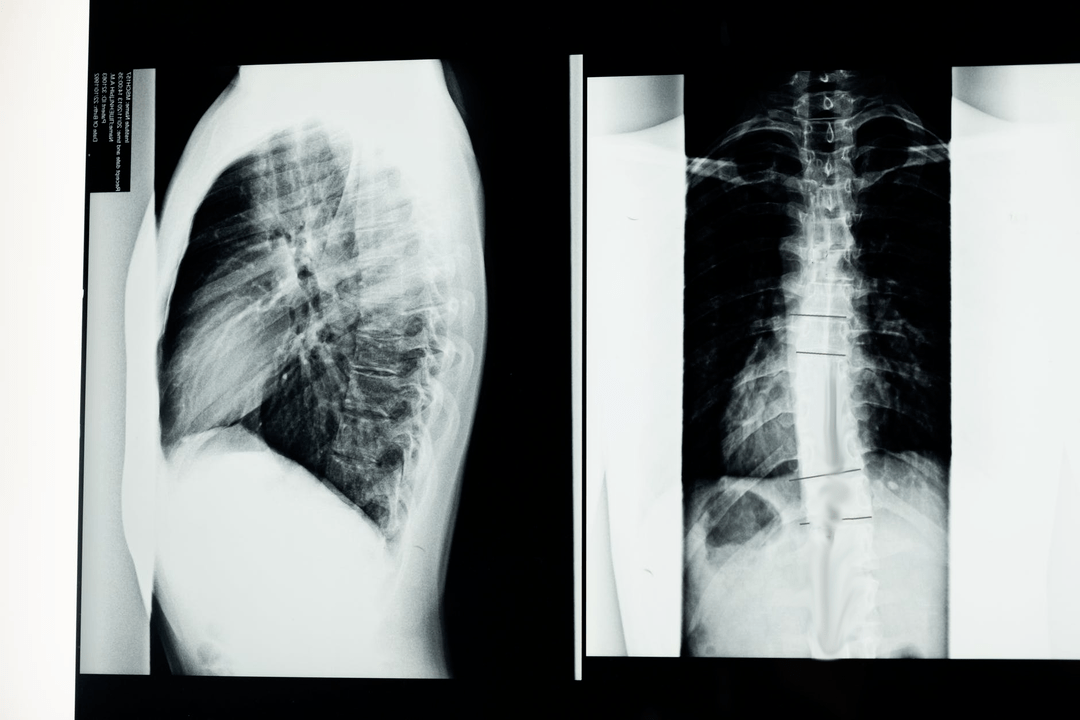

Pirms diagnostikas pētījumu uzsākšanas neirologs apkopo pacienta slimības vēsturi un rūpīgi izpēta viņa sūdzības. Osteohondrozei ir kopīgi simptomi ar dažām citām slimībām, tāpēc ir svarīgi spēt atšķirt patoloģijas. Rentgena pētījumi palīdzēs apstiprināt osteohondrozes diagnozi: radiogrāfija, mielogrāfija un datortomogrāfija.

Aptaujas rentgens ļauj iegūt mugurkaula vai tā daļas rentgena attēlu. Tādā veidā ārsts var noteikt slimības skarto vietu. Skaidrības labad mēs paskaidrosim, kā ar rentgena palīdzību var noteikt osteohondrozi: attēlā būs redzams starpskriemeļu diska sašaurināšanās, kaulu izaugumi (osteofīti) vai mugurkaula segmenta formas izmaiņas.